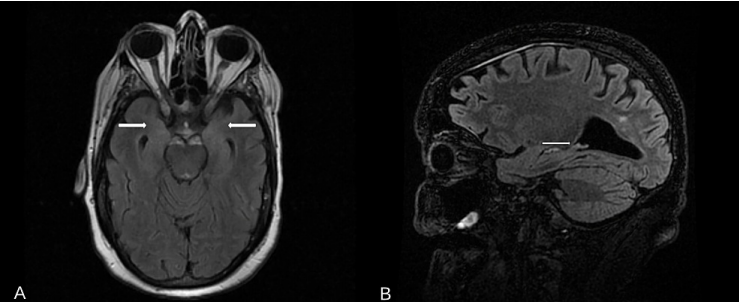

進(jìn)一步的病毒學(xué)檢測(cè)中,丙型肝炎病毒(HCV)、巨細(xì)胞病毒(CMV)、HCV、乙型肝炎抗體和抗原、HIV Ag/Ab和SARS-CoV-2均正常。腦部MRI顯示雙側(cè)海馬有輕度T2高信號(hào)(圖1A、1B)。結(jié)合臨床表現(xiàn)及診斷資料,診斷為電壓門控鉀通道邊緣性腦炎(VGKC-LE)。

圖1:腦MRI T2/FLAIR對(duì)比圖。(A) MRI T2/FLAIR軸位和(B) MRI T2/FLAIR矢狀位。

該病例中,雙側(cè)海馬體內(nèi)的輕度T2高信號(hào)在幻聽和幻視中起著重要作用。大多數(shù)有癥狀的VGKC抗體邊緣性腦炎有皮層下病變,通常累及邊緣系統(tǒng)。與COVID感染引起的腦病相比,自身免疫性腦炎中神經(jīng)絲輕鏈蛋白(NF-L)等軸突損傷的生物標(biāo)志物也顯著升高[14]。